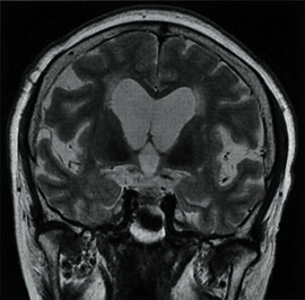

春夏新作モデル 脳血流SPECT統計解析ソフトウェア が新しくなりました (e-ZIS) 科学・サイエンスの詳細情報

脳血流SPECT統計解析ソフトウェア (e-ZIS) が新しくなりました。脳血流SPECT:統計解析による診断のポイント その3。Amazon | 全脳シリーズ Vol.3 秋山仁教授監修 全脳JINJIN 2。106I61 | medu4でゼロから丁寧に医学を学ぶ。